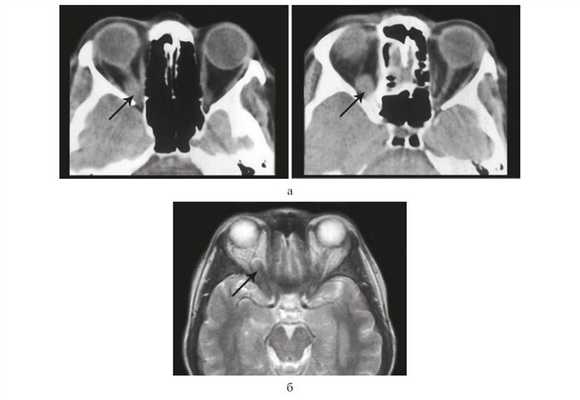

По данным КТ и МРТ головного мозга и глазниц выявлено округлое объемное образование в области канала зрительного нерва, интенсивно и гомогенно накапливающее контрастное вещество (рис. 1).

Рисунок 1. КТ (а), МРТ (б) орбит. В задних отделах правой глазницы определяется овальной формы опухоль (стрелка), плотно охватывающая зрительный нерв и распространяющаяся в канал зрительного нерва.